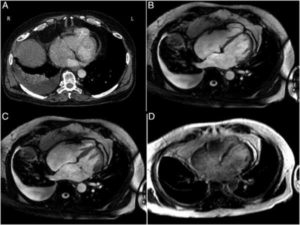

- кардиомиопатии (аритмогенная дисплазия правого желудочка, дилатационная кардиомиопатия, гипертрофическая кардиомиопатия, синдром некомпактного миокарда). Под кардиомиопатиями понимают первичные заболевания миокарда после исключения клапанных, перикардиальных и коронарных болезней. МРТ помогает разграничить ишемическую и неишемическую дилатационную кардиомиопатию. МРТ является инструментом для визуализации редких расположений гипертрофии: в правом желудочке, в апикальном сегменте левого желудочка. МРТ является одним из главных методов в выявлении аритмогенной дисплазии правого желудочка (АДПЖ). Главные признаки АДПЖ на МРТ: локальное нарушение сократимости ПЖ, дилатация ПЖ, усиление трабекулярности ПЖ и отсроченное контрастирование миокарда ПЖ

- диагностика миокардита. Миокардит визуализируется с помощью МРТ с контрастным усилением, как зоны гиперусиления с интрамуральной и субэпикардиальной локализацией. Так же можно определить воспалительный отек тканей сердца.

- оценка жизнеспособности миокарда (после острого инфаркта миокарда, перед хирургическим лечением). МРТ можно применять для выявления очагов острого инфаркта миокарда, оценки перфузии миокарда, но чаще используют для выявления рубцовых изменений миокарда (ПИКС), осложнений инфаркта миокарда (аневризмы, внутрижелудочковых тромбов).

- заболевания перикарда. При выполнении МРТ сердца можно определить толщину фиброзного утолщения перикарда, выявить наличие выпота в полость перикарда.

- опухоли сердца. Самой частой доброкачественной опухолью сердца является миксома. Миксома сердца обычно развивается из межпредсердной перегородки, имеет относительно однородную структуру с четкими границами. При МРТ с внутривенным контрастированием миксома часто негомогенно накапливает контрастный препарат.